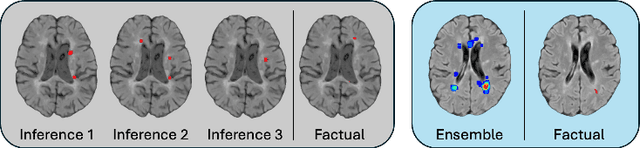

Abstract:Image-based personalized medicine has the potential to transform healthcare, particularly for diseases that exhibit heterogeneous progression such as Multiple Sclerosis (MS). In this work, we introduce the first treatment-aware spatio-temporal diffusion model that is able to generate future masks demonstrating lesion evolution in MS. Our voxel-space approach incorporates multi-modal patient data, including MRI and treatment information, to forecast new and enlarging T2 (NET2) lesion masks at a future time point. Extensive experiments on a multi-centre dataset of 2131 patient 3D MRIs from randomized clinical trials for relapsing-remitting MS demonstrate that our generative model is able to accurately predict NET2 lesion masks for patients across six different treatments. Moreover, we demonstrate our model has the potential for real-world clinical applications through downstream tasks such as future lesion count and location estimation, binary lesion activity classification, and generating counterfactual future NET2 masks for several treatments with different efficacies. This work highlights the potential of causal, image-based generative models as powerful tools for advancing data-driven prognostics in MS.